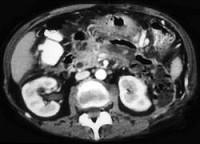

问题 女性,34岁,寒战、高热、急性中上腹偏左腹痛,压痛,CT扫描如图,最可能的诊断是 ( )

选项 A.急性胰腺炎 B.胰腺脓肿 C.慢性胰腺炎急性发作 D.胰腺癌 E.胰腺转移癌

答案 B